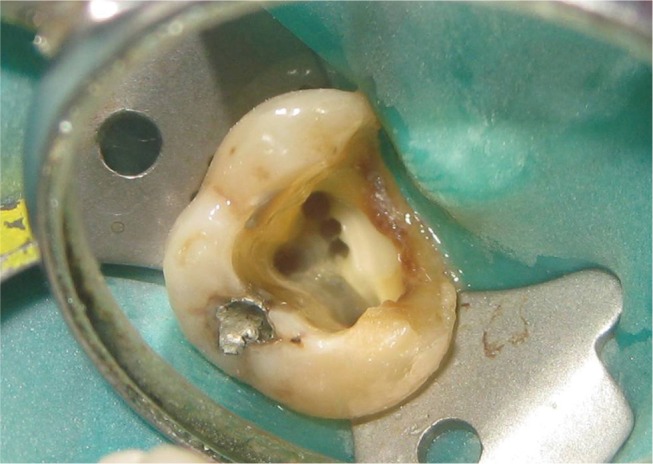

Subsequent to anesthesia and rubber dam isolation, access cavity preparation was initiated and the mesiobuccal, distobuccal, and palatal canals were located. Anticipating the presence of extra canals, further exploration was carried out deliberately and two sticky points were located. This led to finding of two additional canals in the mesiobuccal root on the line connecting the mesiobuccal and palatal canal orifice (Figure 1). Magnifying loupes (2.5X, ST250, STAC Dental Instruments Inc., Brampton, Canada), a DG 16 endodontic explorer, and sodium hypochlorite were the adjuncts used to locate the canals. After locating the orifices, an attempt was made to understand the internal anatomy of the mesiobuccal root using K files and intraoral periapical radiographs. While negotiating the canals individually in the mesiobuccal root, there was no hindrance in the movement of the #10 K file in any of the three canals. However, simultaneous insertion posed obstruction in the vertical movement of the files in the 2 extra canals. The above finding raised an element of doubt regarding the configuration of the canals. Intraoral periapical radiographs were taken from three different horizontal angulations (Figures 2a, 2b and 2c). However, all of the radiographs suffered from overlapping of the endodontic files radiopacity. Only a mesially angulated radiograph revealed limited information on where files associated with the second and third mesiobuccal canals were seen to be meeting in the middle third of the root approximately and continue to merge with the file in first mesiobuccal canal (Figure 2b). To avoid any missed canals, and for better understanding of the tooth's internal anatomy, a MDCT (Brilliance CT 64-channel, Philips Healthcare, Andover, MA, USA) scan was suggested because cone-beam computed tomography (CBCT) was not available in the set up or in the vicinity. The interpretation regarding the number of separate orifices and canals present in the coronal third or at the orifice level was inconsistent with the clinical or radiographic findings. In contrast to the 3 orifices and canals, clinically and radiographically, MDCT revealed only 1 large canal (Figure 3a). In the middle and apical third, 2 canals and 1 canal respectively could be distinguished in both radiographic and MDCT images (Figures 3b and 3c).